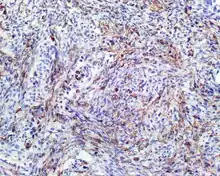

- S100 protein (a tumor marker protein) is focal, patchy to diffuse in all tumors.

S100 protein reaction in a biphenotypic sinonasal sarcoma - Smooth-muscle actin or muscle-specific actin is seen in nearly all tumors, but a strong and diffuse reaction with SMA is seen in only about 50% of cases.